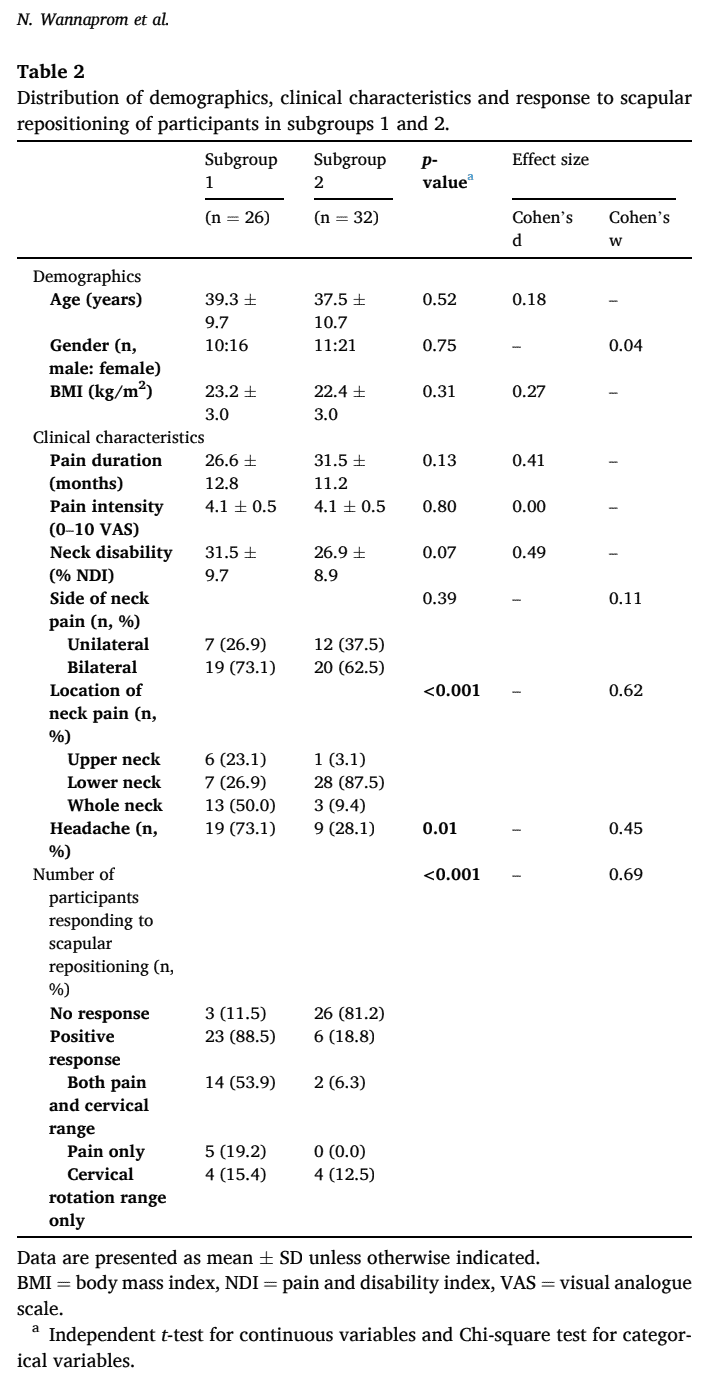

在本次研究中,有 58 名参与者同意参与。 其中 29 人是响应者,因为他们之前在肩胛骨复位后对颈部疼痛和活动范围产生了积极的效果。 有 29 人被列为无应答者。 样本中约 60% 为女性,平均年龄为 38 岁(+/- 10 岁)。 他们的颈部疼痛强度在 VAS 值上为 4.1 (+/- 0.5),颈痛残疾指数为 29.0 (+/-9.4)。

根据 3D 测量结果确定了两个分组。 在分组 1 中,参与者的锁骨回缩和肩胛骨下旋幅度更大。 在亚组 2 中,锁骨隆起增加,肩胛骨更加前倾和内旋。 第 1 分组更经常报告头痛,上颈部或整个颈部的疼痛更严重,而第 2 分组报告的疼痛更多发生在下颈部。 在所有其他结果(人口统计学、颈部疼痛强度、持续时间和残疾程度)方面,各亚组的结果相同。

考虑到颈部疼痛患者对肩胛骨复位的反应,本研究发现,88.5% 的亚组 1 参与者做出了积极反应,而亚组 2 中的 81.2% 没有做出积极反应。

你能从这些结果中得出什么结论? 经常报告头痛且上颈部疼痛较重的慢性颈部疼痛患者可能会对针对肩胛骨复位的干预措施产生良好反应。 在这项研究中,他们表现出更多的肩胛骨下旋和锁骨后缩。 这可能意味着他们的上斜方肌缩短,上斜方肌延长,斜方肌的三个部分和前锯肌无力。 提上睑肌附着在 C1-C4 上,这或许可以解释为什么这些患者更频繁地报告头痛和上颈部疼痛。 作者推测,这可能是导致上颈部负荷增加的原因。

这项研究根据肩胛骨方向的三维测量结果,在慢性颈痛患者中发现了两个不同的亚组。 肩胛骨向下旋转和锁骨内收较多的一组对肩胛骨复位有反应,而锁骨抬高、内旋和肩胛骨前倾较多的一组对颈部疼痛的肩胛骨复位无反应。 此外,有反应的人颈部上部疼痛和头痛较多,而没有达到良好反应的人颈部下部疼痛较多。 这可能会对您选择这些患者的治疗方案起到重要作用。